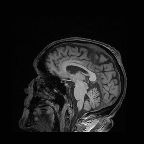

Multi-modality (or multi-channel) imaging is becoming increasingly important and more widely available, e.g. hyperspectral imaging in remote sensing, spectral CT in material sciences as well as multi-contrast MRI and PET-MR in medicine. Research in the last decades resulted in a plethora of mathematical methods to combine data from several modalities. State-of-the-art methods, often formulated as variational regularization, have shown to significantly improve image reconstruction both quantitatively and qualitatively. Almost all of these models rely on the assumption that the modalities are perfectly registered, which is not the case in most real world applications. We propose a variational framework which jointly performs reconstruction and registration, thereby overcoming this hurdle. Numerical results on simulated and real data show the potential of the proposed strategy for various applications in multi-contrast MRI, PET-MR, and hyperspectral imaging: typical misalignments between modalities such as rotations, translations, zooms can be effectively corrected during the reconstruction process. Therefore the proposed framework allows the robust exploitation of shared information across multiple modalities under real conditions.